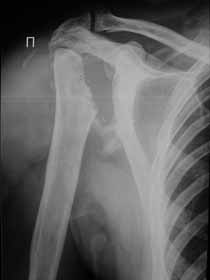

Re: Лизис костей плечевого сустава

Нужна открытая биопсия. будет саркома.

Извиняюсь, что-то фотографии сразу не прошли. сейчас исправимся.